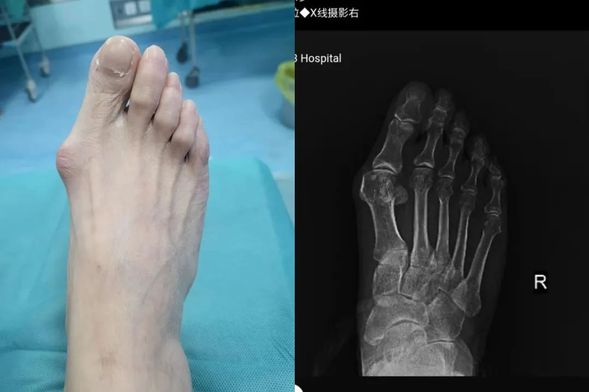

术前,拇外翻严重影响生活

拇外翻,俗称“大脚骨”,是一种常见的足部畸形疾病。当拇外翻角大于15°,跖间角大于10°,并结合患者的临床表现,即可诊断为拇外翻。随着病情发展,患者会出现穿鞋困难、疼痛难忍等症状,严重影响日常生活质量。